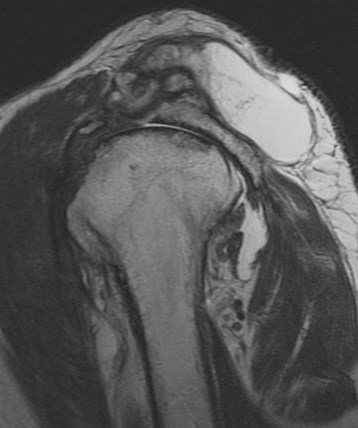

Figure 1 for case Geyser phenomenon

Figure 1